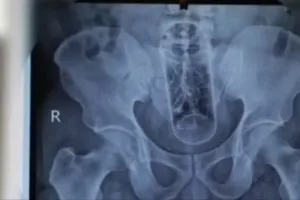

Phẫu thuật cấp cứu lấy chai nhựa dài 20cm trong hậu môn người đàn ông